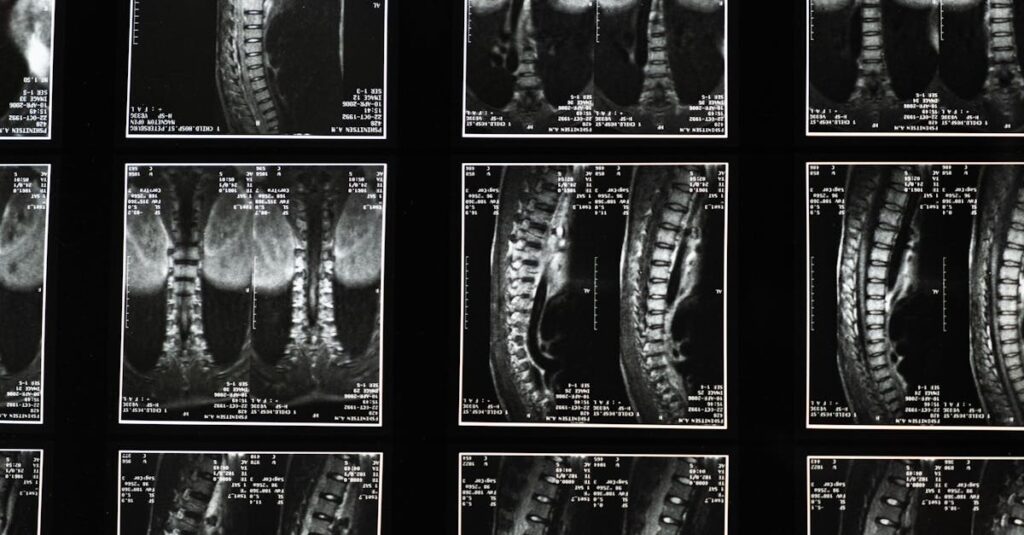

Une IRM ou une radiographie est généralement recommandée pour évaluer l’état de la colonne vertébrale.